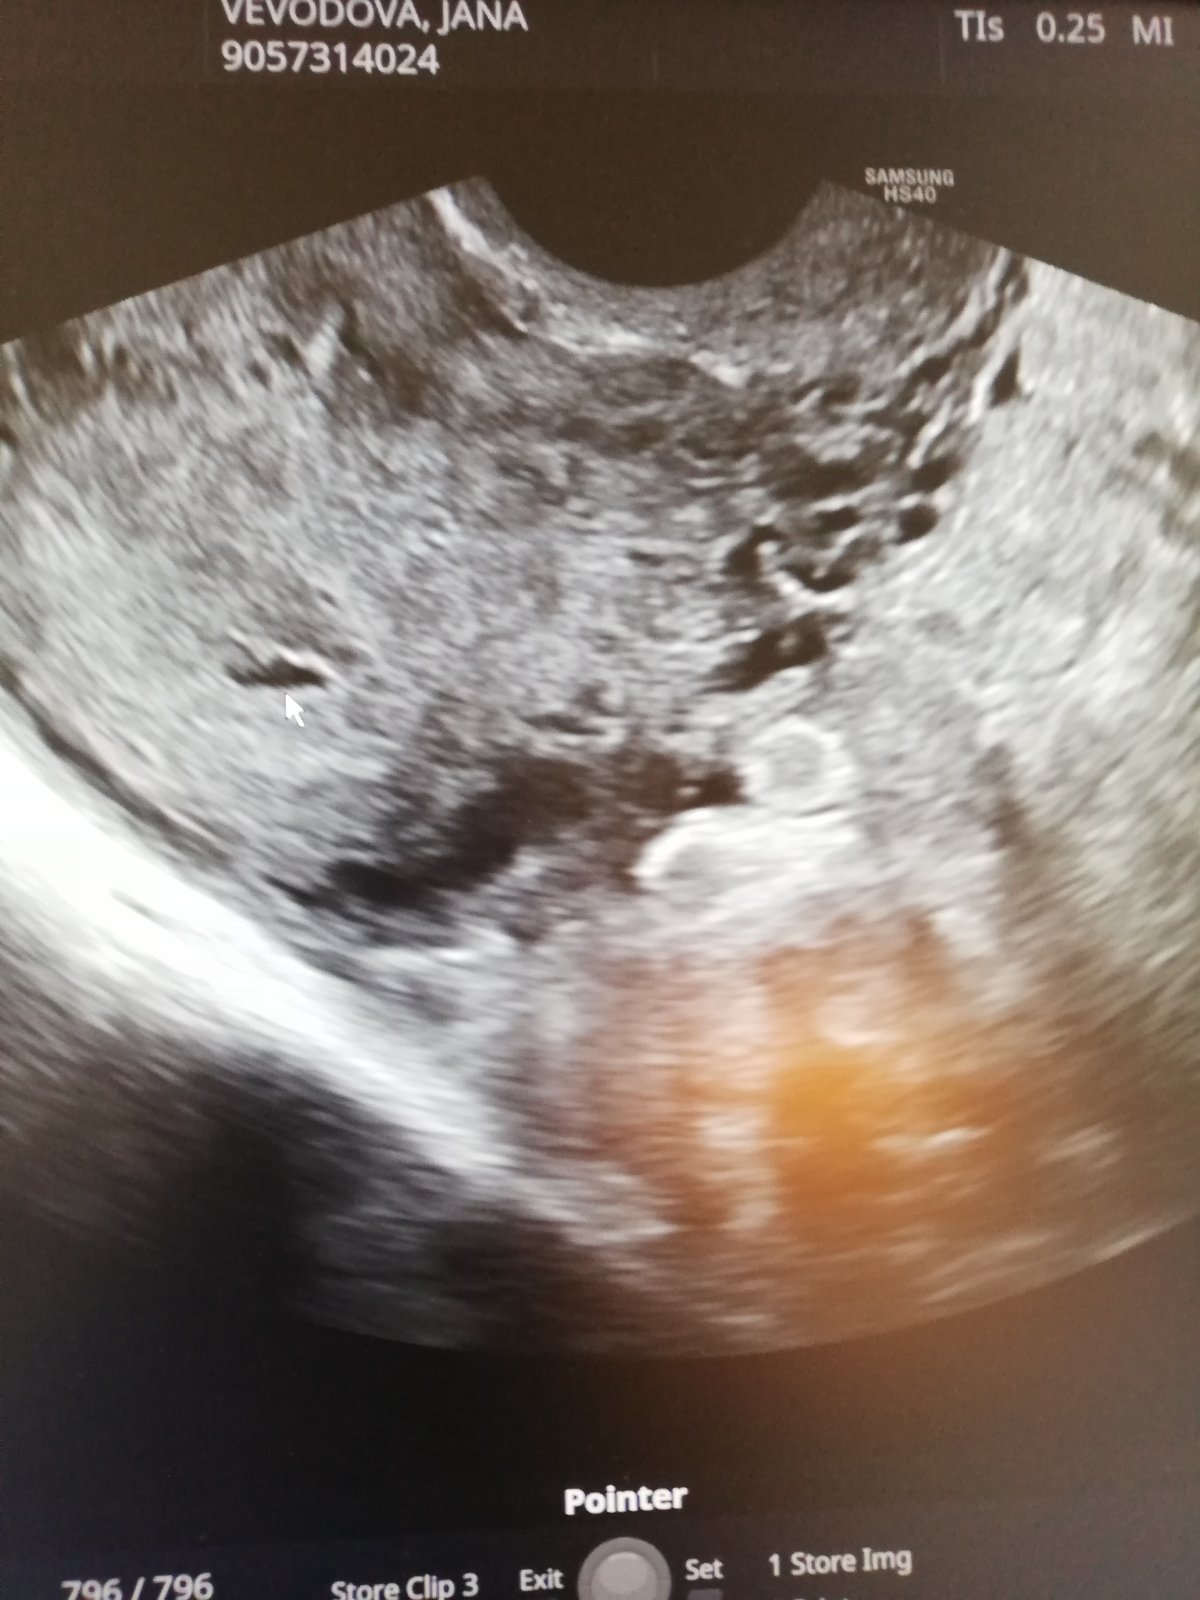

@renat23 jinak tady u té šipky je ta dutinka 😅.